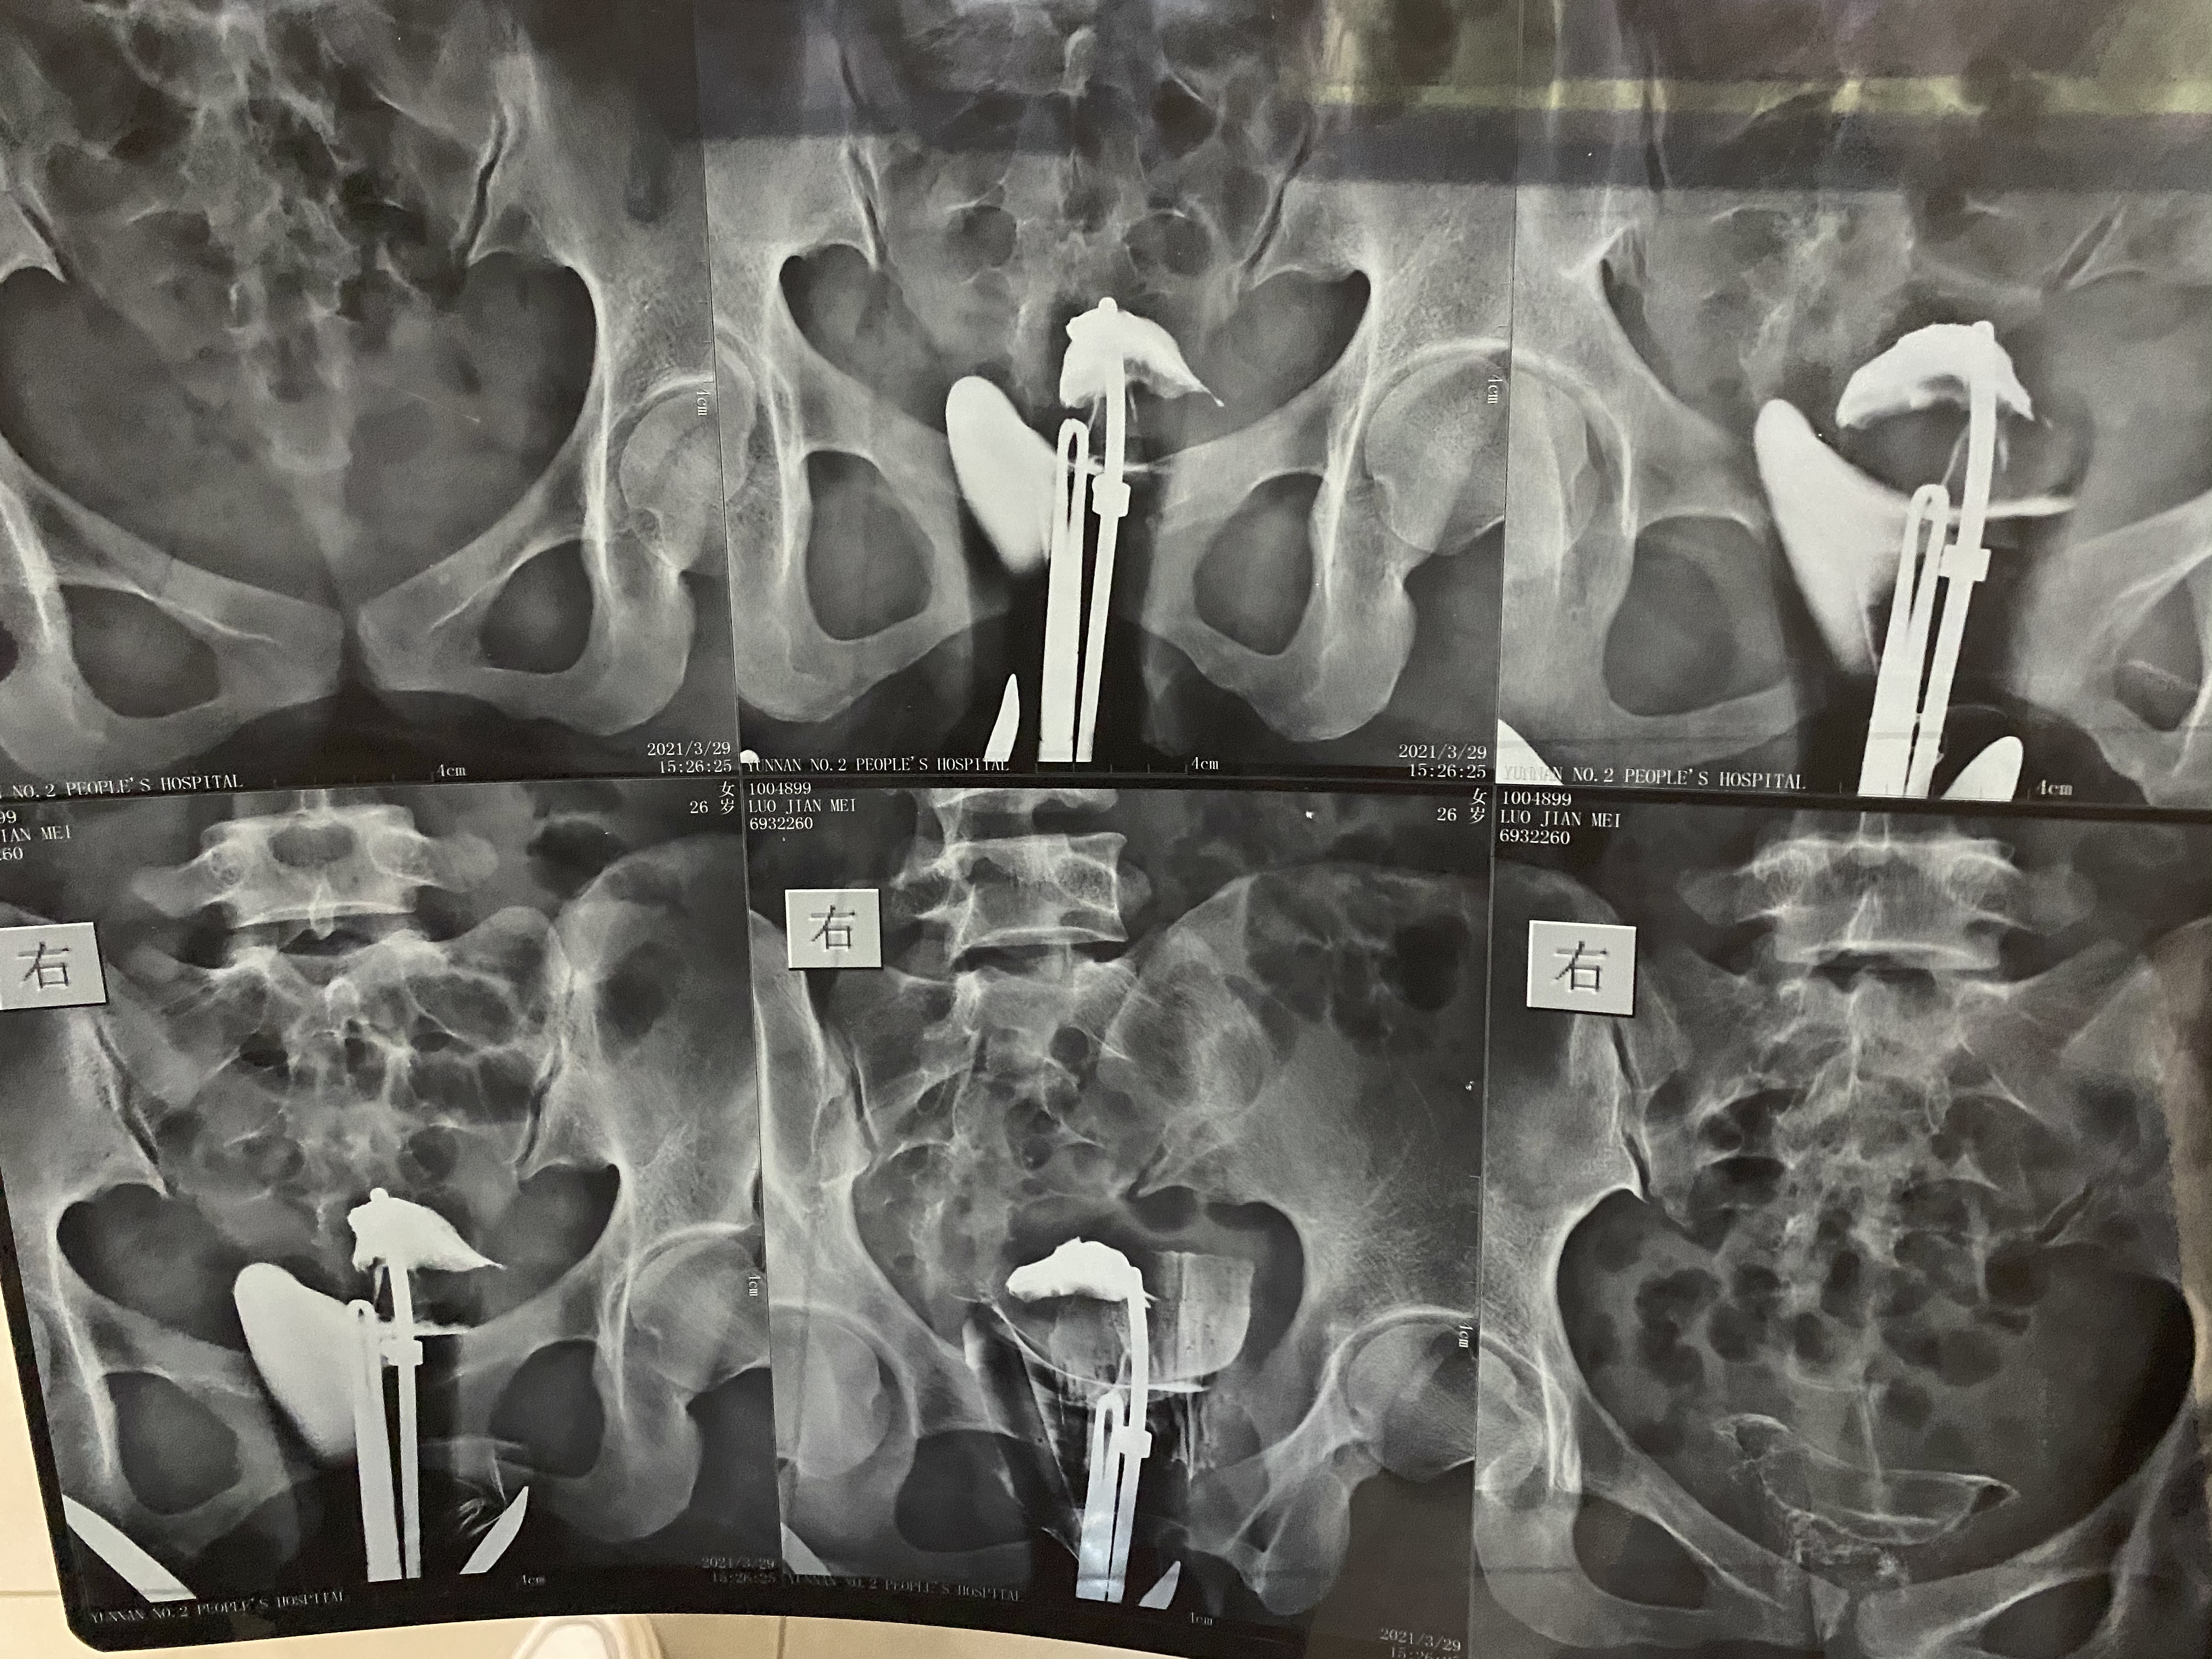

备孕多年未怀孕(原发不孕),本月做输卵管造影,报告显示输卵管堵塞,请问根据片子来看,堵塞的程度是哪种?需要怎么治疗?

你好,片上看输卵管间质部左右开始堵塞,建议做试管!

ღ᭄ꦿ °深海屿鹿এ⁵²º᭄এ 回复 陆海渊:那如果做腹腔镜手术能疏通吗?因为我是hiv患者,不能试管。所以只能自然怀孕

你好,堵的部位在近端,腹腔镜疏通成功的机率低!

在间质部阻塞,可以选择宫腔镜下导丝疏通术。